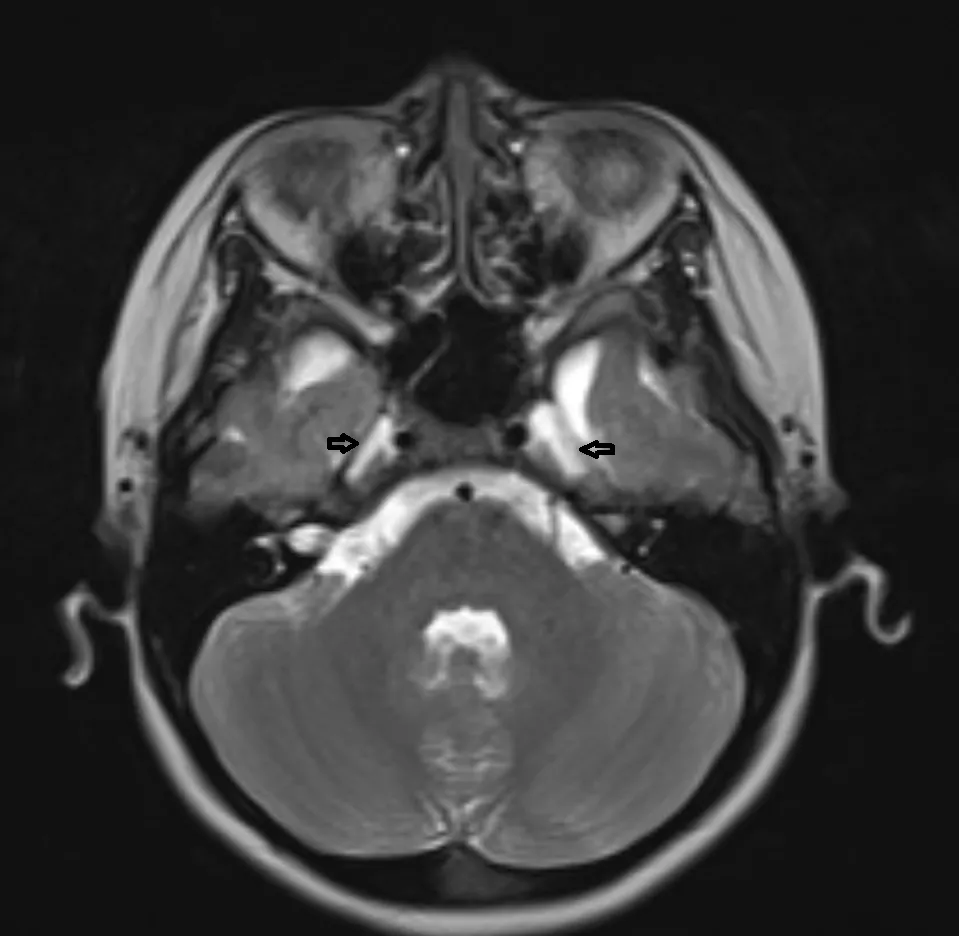

梅克尔(Meckel)腔不对称

梅克尔腔呈半月形或卵圆形,左右各一,位于颞骨岩尖部前方、海绵窦后部外下方,由颅后窝突入颅中窝后内侧的硬脑膜陷窝形成。正常Meckel腔的长轴在横断面朝向前内,在冠状面朝向内上,呈两侧对称的「八」字形。Meckel腔在矢状面呈「C"字形,开口朝后,越过岩尖与桥前池相交通,交通处即三叉神经孔。Meckel腔内含有脑脊液、三叉神经节及神经纤维。

双侧Meckel腔的大小一般基本对称,可出现大小不对称或一侧Meckel腔增大。单纯的双侧Meckel腔不对称通常无临床意义。但应注意观察增大一侧的Meckel腔内是否存在异常信号、三叉神经束有无增粗。

CASE1

双侧Meckel对称

CASE2

双侧Meckel不对称